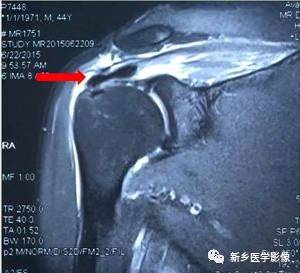

病例二:

红色箭头:冈上肌腱近止点撕裂,大小约1cm